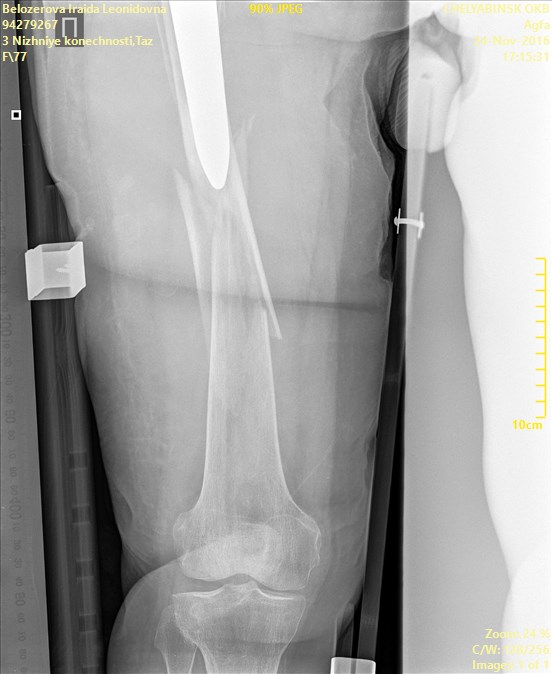

ÎÏÖËÁ   ó÷î   10(ã×ÁÊÍÀÌÌÅÒ)íÁÔÉÓ.   ðÏ   ÎÁÛÉÍ   ÉÚÍÅÒÅÎÉÑÍ  ÏÔ

ÍÅÖÍÙÝÅÌËÏ×ÏÊ ×ÙÒÅÚËÉ ÄÏ ËÏÎÃÁ ÎÏÖËÉ 204ÍÍ. îÏÇÁ ÐÒÁ×ÁÑ

Name: Belozerova_Iraida_Leonidovna_BEDRENNAYA_AP_CR.jpg